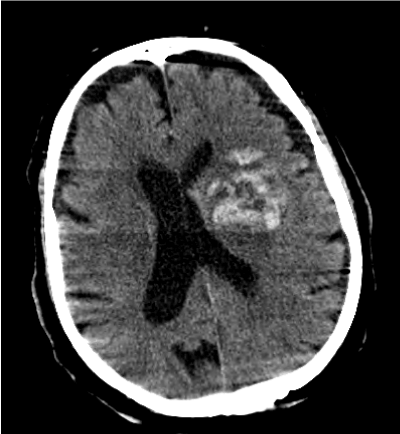

We explored the effects of INR on the volume changes. Assuming similar baseline volume and similar time since baseline CT, every 1 point increase in INR was associated with a median increase of 2.36 ml (95% CI 0.46 – 4.26, p= 0.024) in hematoma expansion measured as the change from baseline in volume (Figure 1-4). Given the imbalance in proportion of hypertension, pre-admission mRS, GCS and age between the included and excluded groups, we investigated the effect of INR adjusted for the variables by inclusion in the median regression model in addition to other covariates, the association between INR and hematoma growth remained significant with an effect size of 1.92 ml (95% CI 0.46- 3.37, p=0.01) (Table 3).

Figure 3. First CT Scan of the Patient with Higher INR Value (INR5.4)

Figure 4. Second CT Scan of the Patient with Higher INR Value (INR5.4)